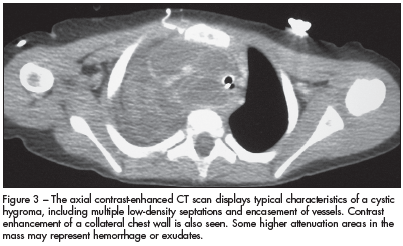

In the presence of trauma or an upper respiratory tract infection, a cystic hygroma often becomes infected and grows rapidly, a process that produces fever and pain. Infiltration of the mass into the floor of the mouth, base of the tongue, epiglottis, or mediastinum can compromise the airway. This rapid enlargement of the mass secondary to infection accounts for the clinical signs and symptoms. In addition, our patient's clinical findings were consistent with superior vena cava syndrome (venous congestion, dysphonia, dyspnea, and dilated chest wall veins), which eventuated from thoracic compression of the hygroma (Figure 3).

The diagnosis of an infected cystic hygroma can be difficult because other processes--including retropharyngeal abscesses and infected branchial cleft cysts--also present with a neck mass, fever, and stridor. In many cases, advanced imaging is necessary to confirm the diagnosis. CT or MRI of a cystic hygroma typically reveals a multiloculated cystic mass. CT can delineate the size of the mass, although MRI more reliably identifies extension into the soft tissues, particularly neurovascular structures.